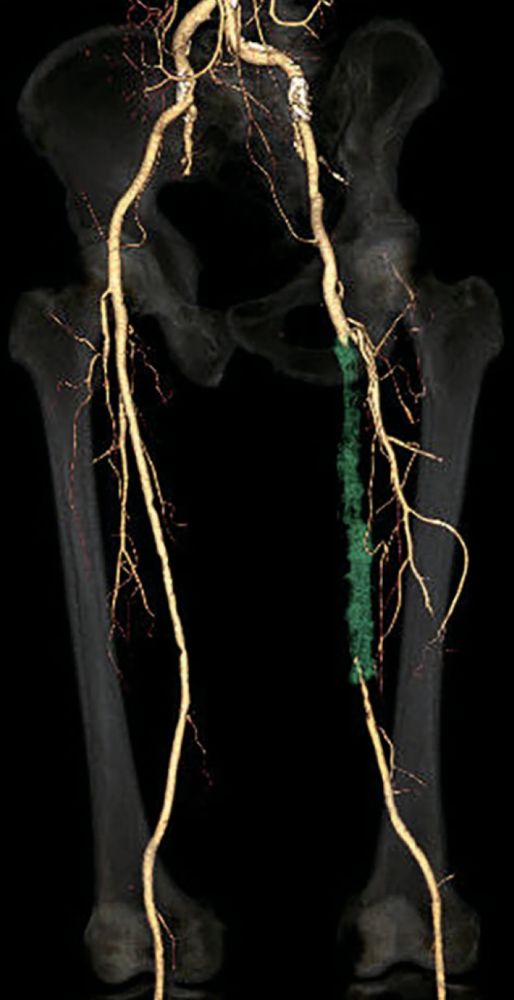

- 対象病変部位(図1): 左 SFA 閉塞(病変長約22 cm)

- IVUSにて遠位部のヘルシーな部分をマーキングし、バイアバーン® ステントグラフト径6.0/長250 mm を留置(図2)。

- 造影上は良好な血流改善を得られたが、IVUSではSFA起始部にプラーク残存を認めた(図3)。

- プラークをフルカバーするため、SFA起始部にバイアバーン® ステントグラフト径6.0/長50 mmを追加留置(図4)。

- 径6.0/長150 mm高圧バルーンにて高圧拡張を追加し、DFAの血流も問題がないことを確認して手技終了(図5)。